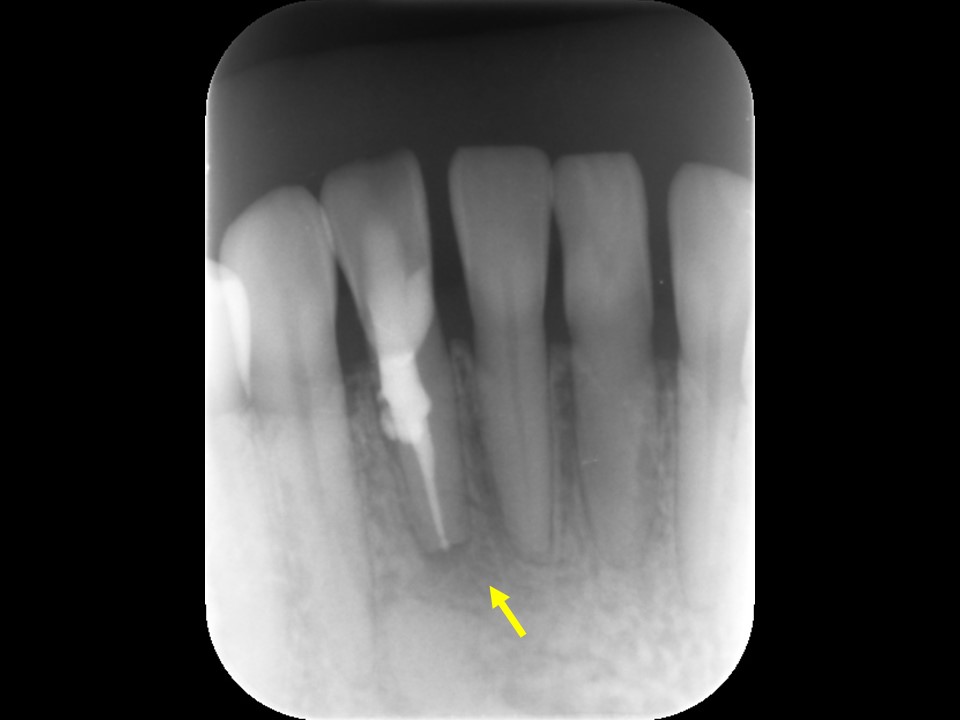

診断と治療計画の立案

当該の左下7番の奥歯はクラウンで被せてありましたが、頬側に歯茎の腫れ(フィステル、サイナストラクト)を認めました。レントゲンおよびCTによる診査を行ったところ、すでに根管治療が施してあるものの根管充填が不十分で、根尖病変を生じていました(下写真)。また、歯根の先端部分にはファイルと思われる器具の破折片を認めました(矢印)。根管内部へのバクテリアの感染による慢性化膿性根尖性歯周炎と診断し、再根管治療をおこなうことにしました。

治療前のレントゲンおよびCT画像です。当該歯はすでに根管治療が施してあり、根尖部には根尖病変によるX線透過像を認めます。

また、根尖部にはファイルと思われる器具の残存を認めます(矢印)。